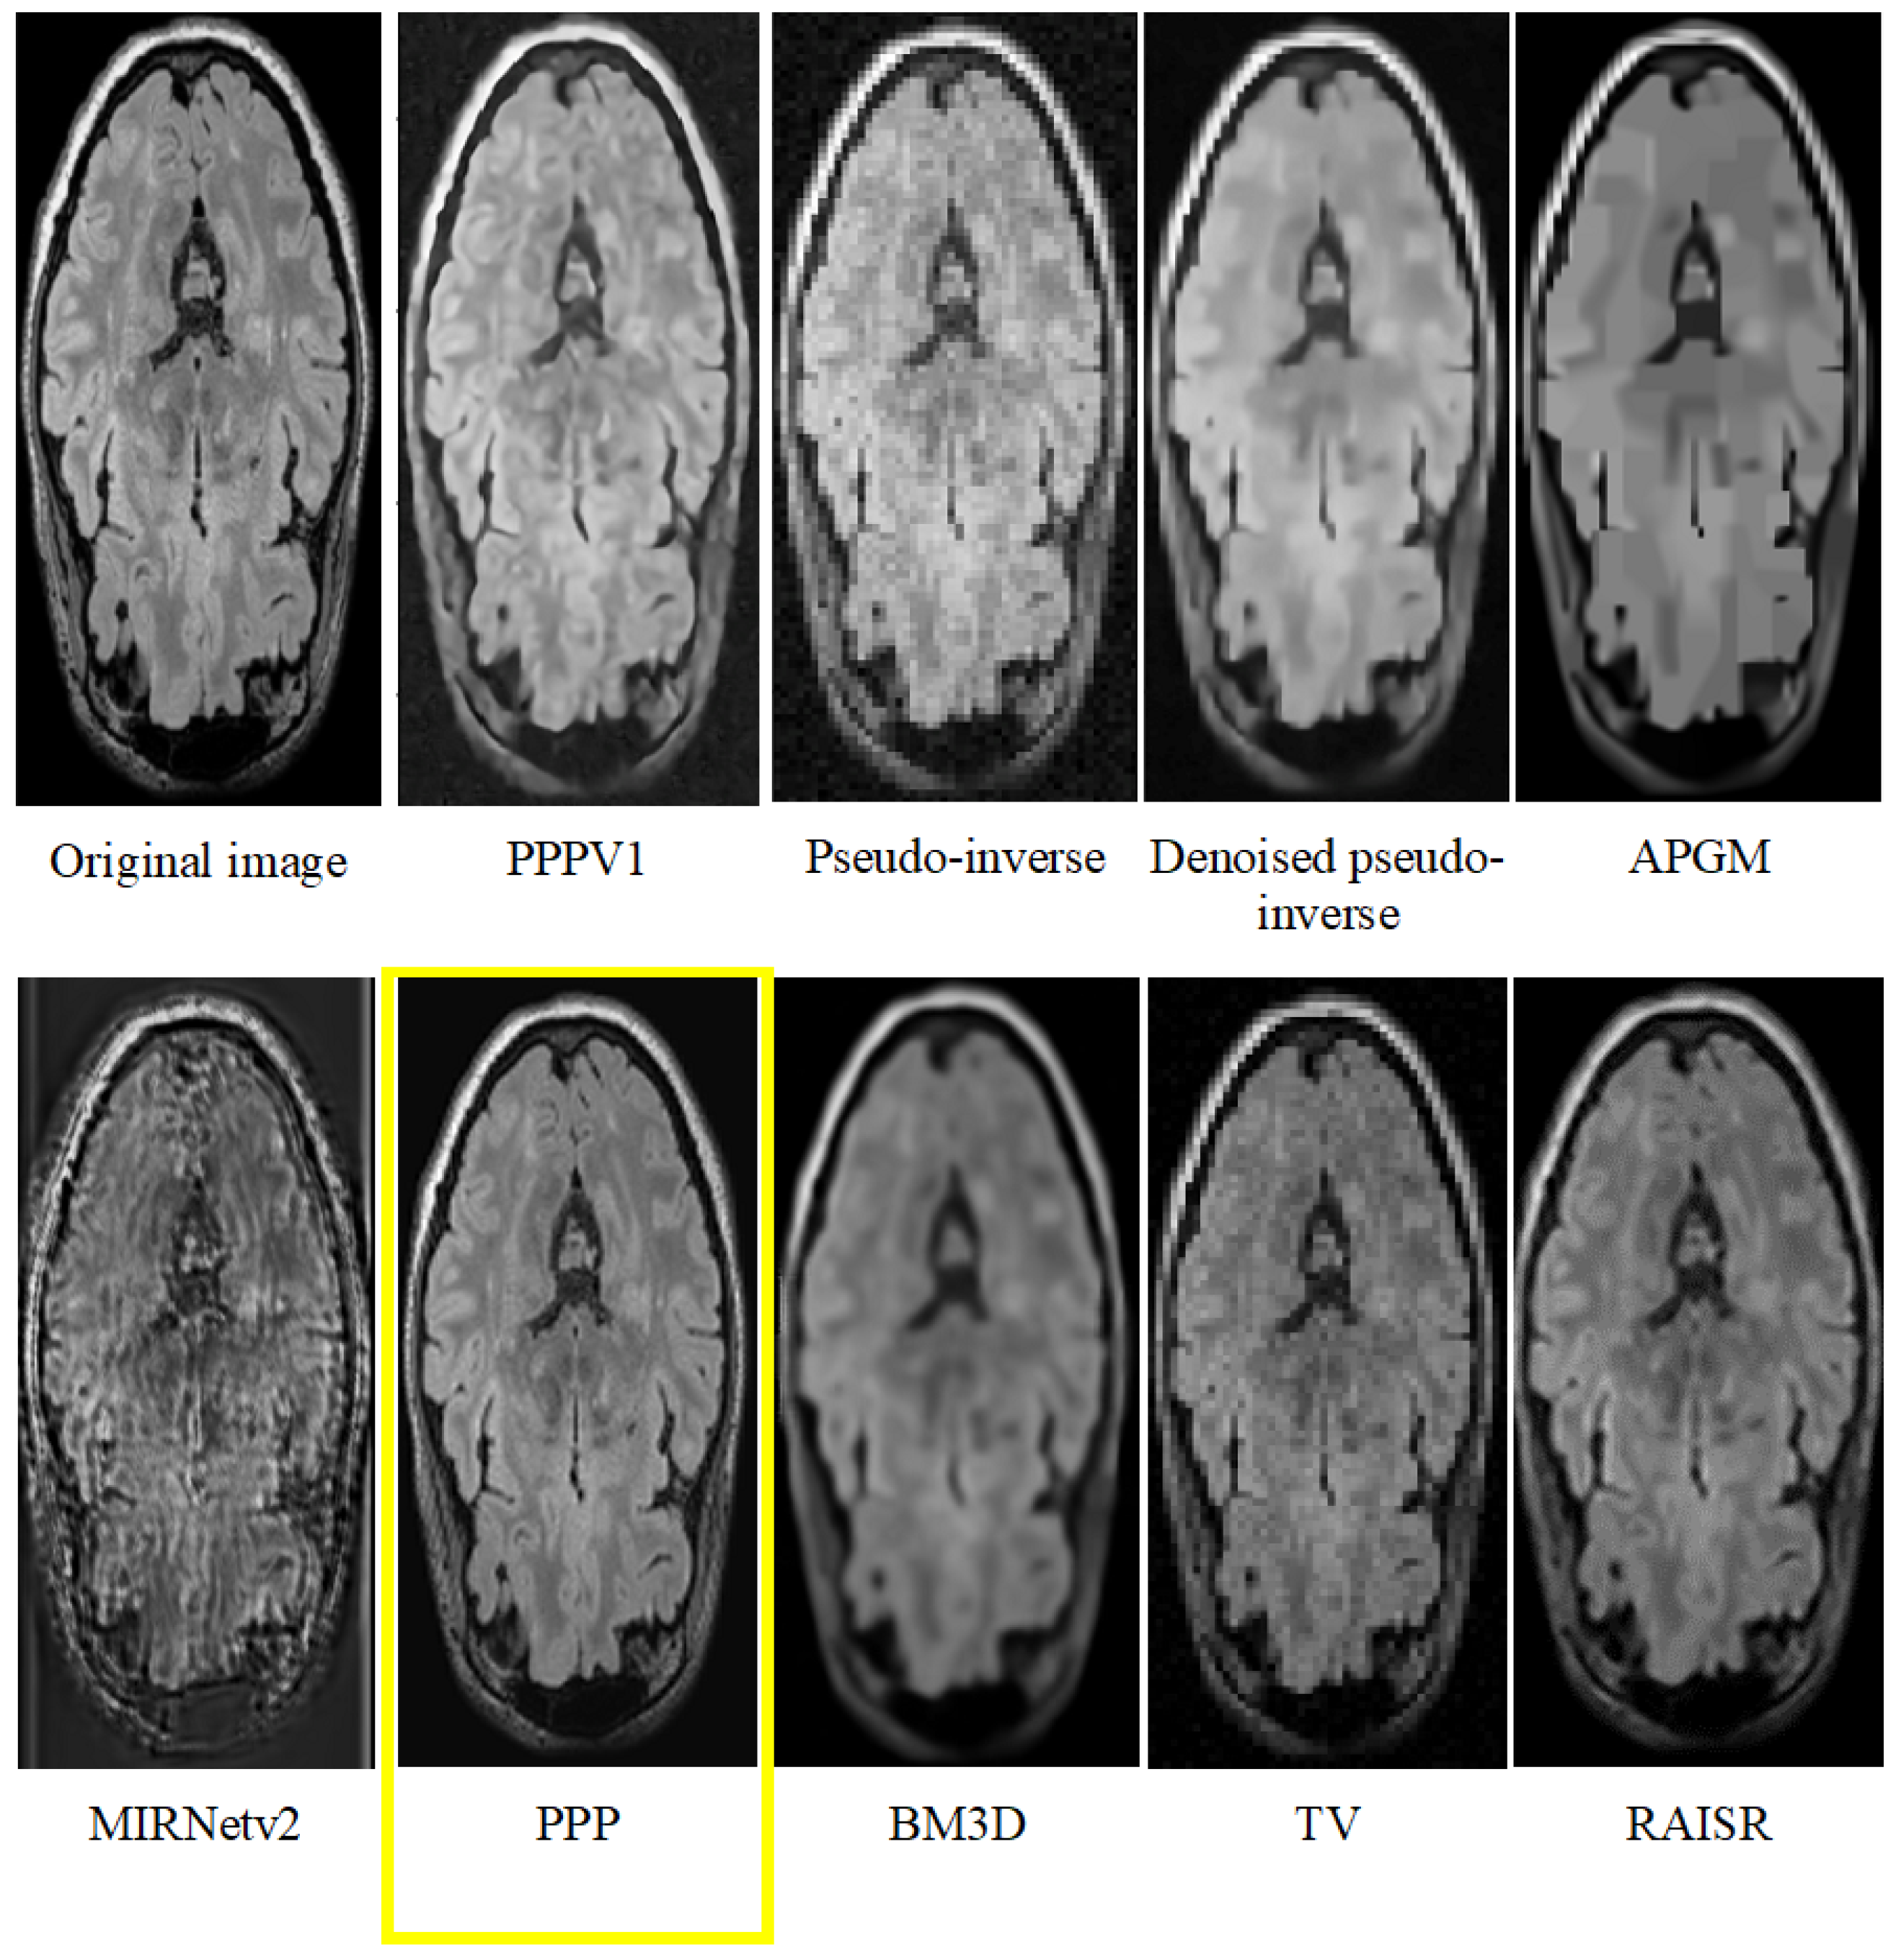

- The experimental results demonstrate the superiority of our approach over existing techniques, underscoring its potential for clinical applications in neuroimaging.

- The practical implications of our results suggest that our method holds great promise for applications where MRI slices quality enhancement is paramount.